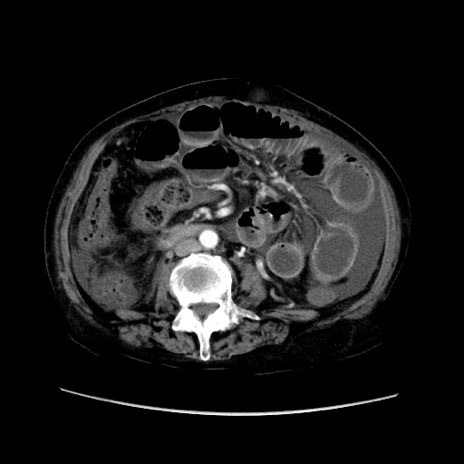

症例31(横断像)

【症例】80歳代 女性

【主訴】腹部膨満感

【現病歴】他院にて肝硬変にてフォロー中。1週間前から便秘、腹部膨満感、臍部腫瘤あり受診となる。

【既往歴】肝硬変

【身体所見】腹部膨隆あり、皮膚変化なし、疼痛なし。

【データ】WBC 4600、CRP 0.25